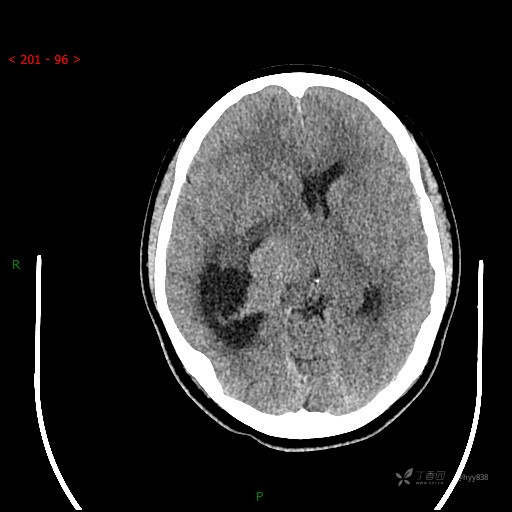

简要病史:患者于1月前无明显诱因出现视物模糊,无明显头痛头晕,无恶心呕吐,无昏迷,无肢体偏瘫等症状,就诊于当地医院头部CT考虑:右侧丘脑、脑室占位。予以对症处置后家属为求进一步诊治来我科,以“颅内占位”收入院。 起病以来,精神、饮食、睡眠欠佳,大小便正常,体力下降,体重无明显变化。

临床诊断:脑室占位

颅脑CT平扫